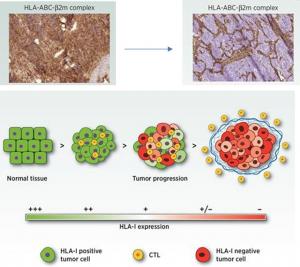

Una investigación del ibs.Granada demuestra el importante papel de unas proteínas para ayudar al sistema inmune a detectar el cáncer

El grupo de investigación de Respuesta Inmune y Cáncer del Instituto de Investigación Biosanitaria de Granada (ibs.Granada), liderado por Francisco Ruiz Cabello, ha demostrado el papel relevante qu